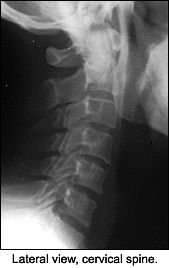

The lateral view isn't very helpful, but the APOM demonstrates a slight depression of the lateral mass of C2 on one side compared to the opposite side. Other than that finding, nothing really appears to be significant. If you didn't have the history, would you have taken the X-rays? If you didn't have the history and the clinical findings, would you have noticed the difference in the lateral masses of C2? It's difficult to say. I'm not certain I would, but the patient had significant discomfort.

So, what would you do now with this information? Perform orthopedic tests, or would you do further imaging? I decided on more imaging because I'm into radiology. I really didn't want to do any orthopedic tests on the patient because having him run through simple range of motion of the cervical spine aggravated his symptoms, so I ordered a CT of the cervical spine. Upon review of the X-rays, we can now see that the APOM was telling us the answer we couldn't see clearly.

On the CT scan through the C1-2 vertebrae, note the fracture through the dens and the lateral mass of C2. (That was the depression we saw on the APOM of the lateral mass.) Should we look at the APOM view again?

This view above evaluates C1-C2, which cannot be visualized clearly on the lateral. The most important element to check is the alignment of the lateral masses of C1. The intervertebral space should be symmetric. The dens can also be evaluated for fracture in this view, but occasionally overlying shadows may give the false impression of a dens fracture (Mach effect). Correlate the findings with the lateral view of the cervical spine. The incidence of fractures to the axis is about 6 percent, and over 50 percent of those fractures involve some part of the dens.